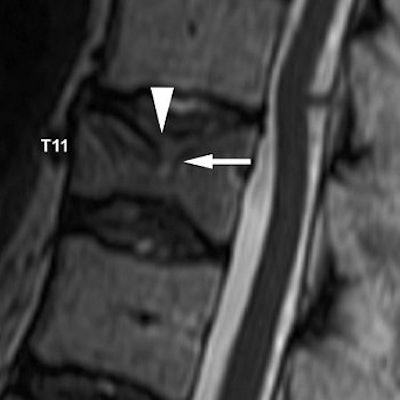

| Same patient as above. Sagittal reformatted CT image after vertebroplasty shows cement leakage in T10-T11 disk space (arrow) through cortical defect seen on preoperative MR image. Hiwatashi A, Ohgiya Y, Kakimoto N, Westesson P, "Cement Leakage During Vertebroplasty Can Be Predicted on Preoperative MRI" (AJR 2007; 188:1089-1093). |